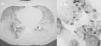

Varón transexual de 30 años, natural de Ecuador, sin hábitos tóxicos, sometido a implantes mamarios de silicona 6 meses antes, que acudió a urgencias por cuadro de 3 días de evolución consistente en disnea de comienzo brusco hasta ser de reposo, fiebre de 38,5 °C, escalofríos y sensación de muerte inminente. En la exploración destacaba temperatura de 37,3 °C, frecuencia cardíaca de 110 lat/min, frecuencia respiratoria de 30 respiraciones/min, sin cianosis, y disminución del murmullo vesicular bilateral; el resto era normal. En la radiografía de tórax se apreciaba patrón alveolar bilateral bibasal y periférico. La gasometría arterial fracción inspiratoria de oxígeno (FiO2) de 0,21 mostró pH de 7,45, presión arterial de anhídrido carbónico (PaCO2) de 35 mmHg, presión arterial de oxígeno (PaO2) de 60 mmHg, saturación arterial de oxígeno del 90% y bicarbonato de 23 mmol/l. En la analítica sanguínea destacaba una cifra de 12.500 leucocitos con fórmula normal; el hemograma, la bioquímica y la coagulación eran normales. Se diagnosticó al paciente de neumonía grave adquirida en la comunidad e insuficiencia respiratoria aguda, y ante la sospecha de infección por el virus de la inmunodeficiencia humana se inició desde urgencias tratamiento con cefotaxima, claritromicina y cotrimoxazol. Con posterioridad refirió que el cuadro había comenzado inmediatamente después de la inyección de 125 ml de silicona líquida en la región trocantérea de los muslos. Además, refería que 4 años antes había presentado un cuadro similar en su país de origen. Se realizó una fibrobroncoscopia en la que no se apreciaron lesiones, así como catéter telescopado en el lóbulo inferior derecho y lavado broncoalveolar (BAL), pero no pudo realizarse biopsia transbronquial debido a que la saturación arterial de oxígeno era del 90% con oxígeno al 50%. En las 12 h siguientes el paciente presentó empeoramiento clínico y gasométrico (FiO2 de 0,5): pH de 7,43, (PaCO2) de 36,1 mmHg, PaO2 de 65 mmHg, bicarbonato de 23 mmol/l y PaO2/FiO2 de 121. En la radiografía de tórax se apreció progresión del patrón alveolar bilateral, por lo que ingresó en la Unidad de Cuidados Intensivos. La tomografía computarizada de tórax mostró patrón alveolar panlobular con broncograma aéreo (fig. 1A). Todas las muestras obtenidas fueron negativas. El análisis del BAL mostró 625 células/ml con un 83% de macrófagos, un 12% de neutrófilos, un 3% de linfocitos y un 2% de eosinófilos. La tinción del BAL mostró inclusiones micro y macrovacuoladas en los macrófagos indicativas de partículas de silicona (fig. 1B), con lo que se confirmó el diagnóstico de neumonitis aguda por silicona (NS) con síndrome de distrés respiratorio. Tras el ingreso en la Unidad de Cuidados Intensivos, se retiraron los antibióticos y se inició tratamiento con 20 mg de metilprednisolona por vía intravenosa cada 8 h y oxigenoterapia a alto flujo sin soporte ventilatorio, con el que el paciente experimentó una gradual mejoría gasométrica. Los hemocultivos, la serología del virus de la inmunodeficiencia humana, el antígeno de Legionella y de neumococo en orina y serología respiratoria fueron negativos. En el momento del alta (día 10 de ingreso) la tomografía computarizada de tórax y la exploración funcional eran normales.

Fig. 1. Corte de la tomografía axial computarizada de tórax realizada durante el ingreso en la Unidad de Cuidados Intensivos, donde se observa el patrón alveolar panlobular con broncograma aéreo (A), y muestra de lavado broncoalveolar que muestra inclusiones micromacrovacuoladas en los macrófagos alveolares (B).